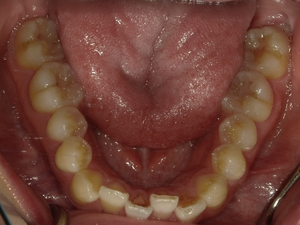

●ご相談内容:歯がガタガタしてる●矯正の種類:マウスピース型矯正「インビザライン」●治療期間:26週間●治療費用:66万円(税込)